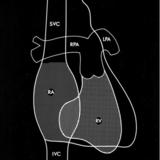

Rt heart